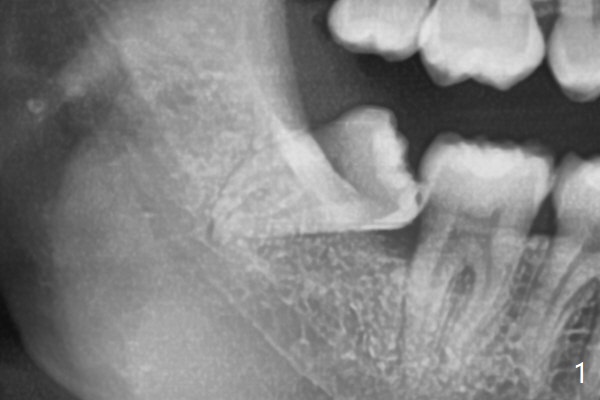

#32 has fused apices, which need sectioning before removal (Fig.1).  A piece of Osteogen plug is inserted to the socket before suturing (Fig.2).